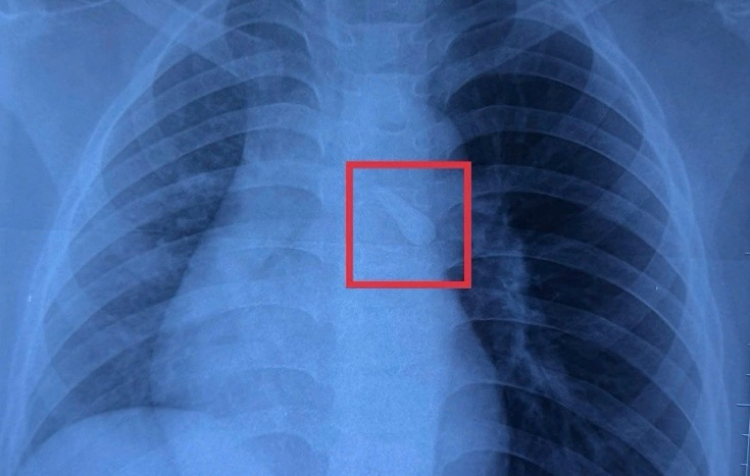

Ghi nhận trên phim Xquang cho thấy bé K. bị sặc dị vật vào khí quản sau tai nạn giao thông, ảnh BVCC

Ghi nhận trên phim X-quang cho thấy bé K. bị sặc dị vật vào khí quản sau tai nạn giao thông - Ảnh: Bệnh viện cung cấp

Kết quả chụp X-quang cho thấy khí quản của bé có một dị vật. Bác sĩ khai thác thêm bệnh sử và phát hiện tại nơi tổn thương vùng hàm mặt ghi nhận bé bị mất răng số 21. Bác sĩ nghĩ đến khả năng va chạm mạnh làm bé bị gãy răng, và hít sặc vào đường thở nhưng bé không cảm nhận được.